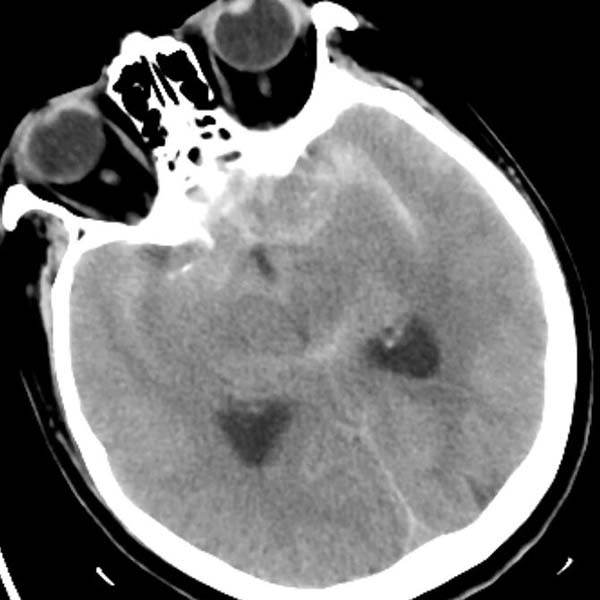

病例二为58岁女性患者。因“突发剧烈头痛伴呕吐3小时”就诊于清华大学附属垂杨柳医院急诊科,行头颅CT检查提示蛛网膜下腔出血。患者嗜睡,频繁呕吐,不排除颅内再出血。为争分夺秒抢救患者生命,神经外科脑血管病介入团队紧急为患者实施了DSA,显示左侧大脑中动脉分叉处宽颈动脉瘤,主要累及下干。术中采取双微导管技术,于动脉瘤内填塞弹簧圈,并置入一枚支架保证致密栓塞和下干分支血管的通畅。成功“拆弹”,化险为夷,患者恢复过程顺利,出院时无神经功能缺损。

▲头颅CT显示蛛网膜下腔出血